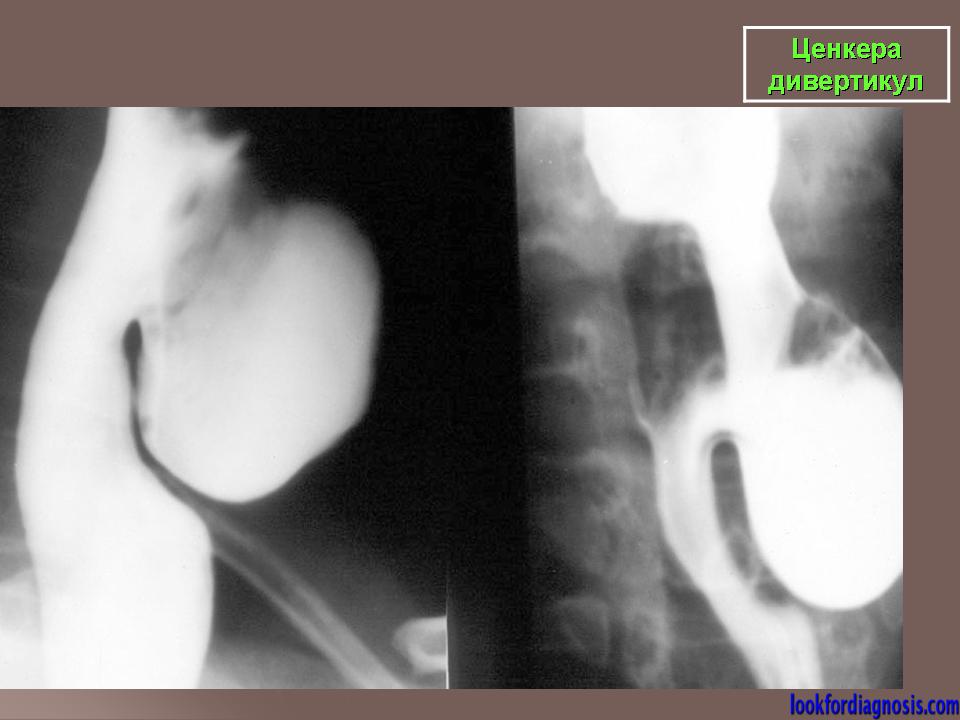

Ценкера дивертикул.

Данная разновидность мешковидных выпячиваний стенки пищевода впервые описана F. A. Zenker и носит его имя, однако о ней упоминал еще К. Людлов в 1764 г.

Barium swallow with fluoroscopy, lateral view</p> <p>During swallowing an outpouching of the posterior hypopharyngeal wall is clearly visualised at the level C5-C6, right above the upper oesophageal sphincter. The pouch is characterized by a narrow neck entrapping some barium after the swallowing.

ID: 12377 Zenker's diverticulum Dr Erik Ranschaert - 18 Nov 2010 Zenker's diverticulum